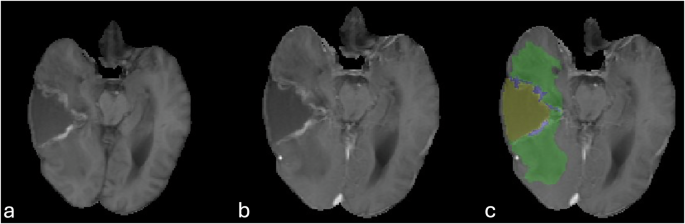

Suboptimal delineation or failure to accurately identify or properly delineate the resection cavity (Fig. 8).

Correction of a suboptimal automated segmentation. Panels (a) and (c) show an example of automated segmentation failure, where the model incompletely outlined the resection cavity. Panels (b) and (d) display the result after manual refinement to ensure the entire cavity was accurately labeled for the ground-truth dataset.